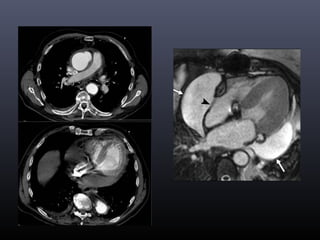

Taponamiento pericárdico

• Signos radiológicos:

Derrame pericárdico

Colapso pared del VD (signo del corazón

aplanado)

Balanceo cardiaco

Movimiento paradójico del septo

interventricular

Dilatación de venas cavas

Compresión del seno coronario

Reflujo de contraste a vena ácigos

No depende exclusivamente del volumen  Presión intrapericárdica >20mmHg